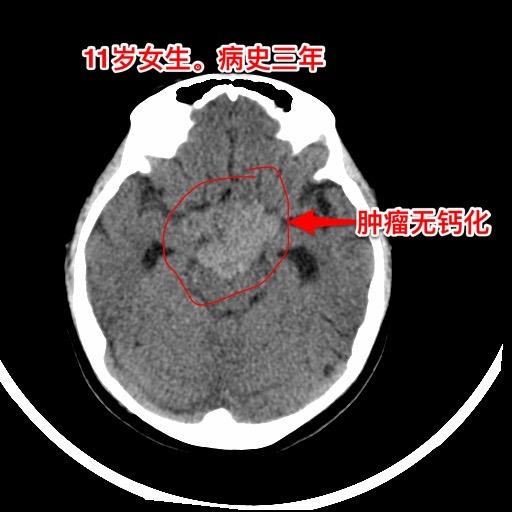

警惕小儿脑肿瘤。小孩子如果长了鞍区肿瘤,一般都会出现症状,一旦有了症状家长及医务人员就要足够重视,才能及时找到病因。 今天介绍的小孩子,肿瘤发现的就晚了。 11岁四川女孩子,因多饮多尿3年半,视力下降9个月,行走不稳、贪睡一个月发现鞍区肿瘤,急忙到北京来就医。 三年前开始出现多饮多尿症状,夜间上厕所好几次,到医院检查没有发现肾脏问题,就没有继续查找原因。 近两年身高增长缓慢,到医院化验显示生长激素缺乏,在当地医院注射生长激素治疗,没有查找生长激素